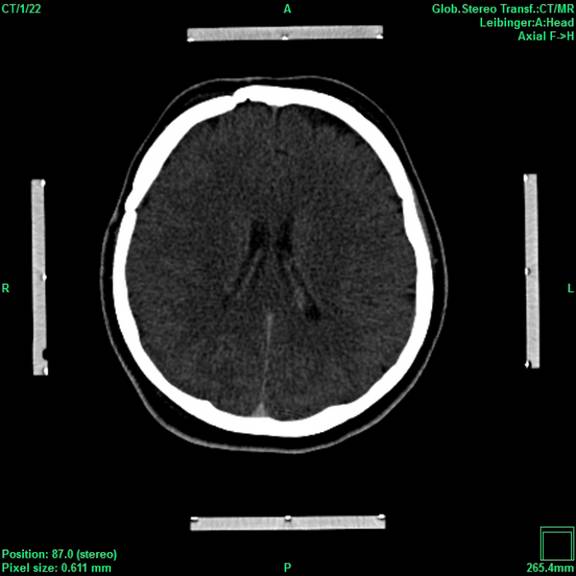

Moderne bildgebende Verfahren in Kombination mit den Entwicklungen im Bereich der elektronischen Datenverarbeitung verhalfen der stereotaktischen und funktionellen Neurochirurgie zum Durchbruch. Denn erst sie ermöglichten präzise und gewebeschonende Eingriffe wie zum Beispiel die Tiefe Hirnstimulation (THS) am menschlichen Gehirn.

Die hohe Qualität der Bilddarstellung zeichnet das inomed Planning System (iPS) aus. Die automatische Zusammenführung verschiedener Bildmodalitäten ermöglicht eine schnelle und sichere Verifikation der geplanten Zugänge. Diese Zugänge sind für eine erfolgreiche THS zwingend notwendig. Auf Wunsch lassen sich anatomische Atlanten über patientenbezogene Daten projizieren. Dies erlaubt wiederum die Verifikation anhand anatomischer Grundlagen.

Ein leistungsstarker mehrstufiger Fusions-Algorithmus ermöglicht das Zusammenführen digitaler Bildinformationen, wobei immer der Erhalt der exakten Patienten-Geometrie im Vordergrund steht, bei gleichzeitiger Optimierung von anatomischer Sichtbarkeit und Bildqualität. Dies bildet die Grundlage für sichere Hochrisiko-Eingriffe wie der THS oder stereotaktisch geführter Biopsien.

Auch postoperative Bildgebung kann nach einem Eingriff wie der THS mit präoperativen Informationen fusioniert werden, so dass Komplikationen ausgeschlossen und die Genauigkeit der THS bestätigt werden kann.

Viele weitere Funktionen vervollständigen das iPS, wie das Messen von Distanzen, Winkeln und Flächen. Für die Verifikation der Trajektorie können die Bilder auf alle typischen Schnittebenen (Sagittal, Coronal, Axial) ausgerichtet werden und zusätzlich entsprechend der Draufsicht der Trajektorie (Perpendicular oder Probe´s eye) oder entlang der Trajektorie eingestellt werden.